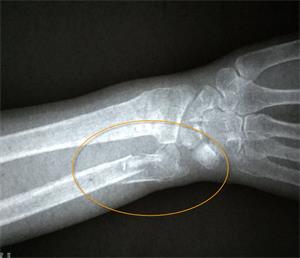

二月十三日,老人在积水潭医院复查拍片时,医生发现老人骨折处竟基本长愈,如图3。医生表示:老人家这个年纪了,一般都骨质疏松,半个月的时间,要想愈合到这种程度,就是年轻人,也是不容易的。并且说:老人的恢复情况确实很好。

'图3'

图3